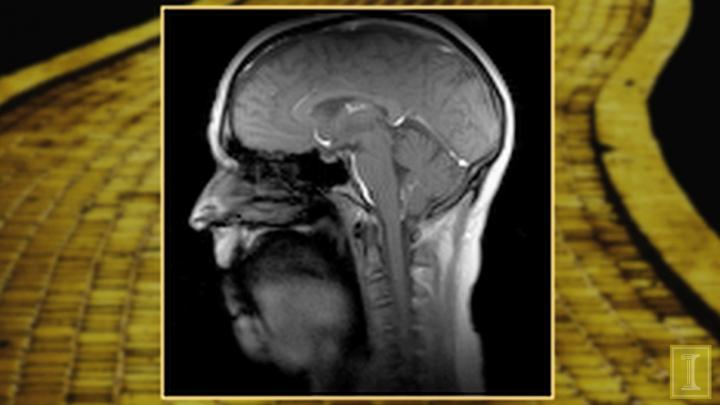

New Real-Time MRI Technique (IMAGE)

Caption

Aaron Johnson, former professional singer and Beckman Institute affiliate faculty member at the University of Illinois, sings "If I Only Had a Brain" from The Wizard of Oz to demonstrate the real-time imaging capabilities of the magnetic resonance imaging (MRI) scanner in Beckman's Biomedical Imaging Center. The technique captures the movements of the voice at 100 frames per second. Despite the excessive noise MRI produces during scanning, the audio in the video is clear because the room is equipped with a special microphone that separates the voice from ambient sounds.

Credit

Beckman Institute for Advanced Science and Technology, University of Illinois